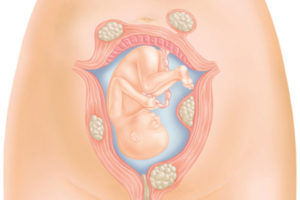

Однако небольшая толщина стенок, плохая растяжимость миометрия, маленькая шейка матки могут быть причиной прерывания беременности из-за гипертонуса матки, истмико-цервикальной недостаточности, отслойки плаценты.

Вследствие чего репродуктивные органы не способны удерживать плод, вес которого постоянно увеличивается. Существует риск прерывания беременности на стадии от 20 до 30 недель.

Маленькая матка при беременности может спровоцировать развитие эмбриона за пределами маточной полости. Терапия направлена на увеличение ее до размеров, позволяющих беспроблемно выносить плод.

Самым опасным в данном отношении является первый триместр. В этот период случается наибольшее число выкидышей. На этапе 2-3 недели происходит имплантация плодного яйца. Ряд неблагоприятных факторов может воспрепятствовать данному процессу.

Помимо недостаточного размера матки к ним относят патологии плаценты, прием некоторых лекарственных препаратов, вирусные заболевания, гормональные нарушения.С 4 по 7 неделю начинают свое формирование все жизненно важные системы и органы малыша. Опасность этого периода заключается в возникновении возможных патологий и аномалий.

На этапе 8-12 недель происходит интенсивное формирование плаценты. Если произойдет ее отслойка, беременность прервется.

Второй триместр считается относительно безопасным. Но и в это время женщина может столкнуться с осложнениями. Опасным является период с 18 по 22 неделю, когда матка стремительно увеличивается в размерах.